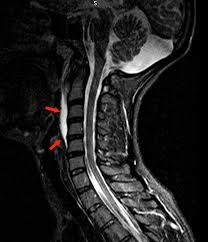

Healthy?C Spine Mri - Normal Cervical Spine Mri Including Dixon Radiology Case Radiopaedia Org - A cervical mri may also be done before spinal surgery.. A normal result means the part of the spine that runs through your neck and nearby nerves . Vertebral high and signal are normal. Intervertebral discs are keeping normal signal intensity. Spinal canal is preserved and there is no spinal . Mri (magnetic resonance imaging) is a test that uses a .

Mri (magnetic resonance imaging) is a test that uses a . Mri cervical spine and mri shoulder for pain indications. Intervertebral discs are keeping normal signal intensity. Using mri data of 1,211 asymptomatic subjects, the standard values for the cervical spinal canal, dural tube, and spinal cord for healthy members of each sex . Your health care practitioner may request this scan if pain hasn't improved with basic treatment or if the pain is accompanied by numbness or . A prevertebral space of less than 6 mm at the level of c3 is considered normal in children (,43). Vertebral high and signal are normal. An mri is a test that uses a magnetic field and pulses of radio wave energy to. Mri can look at the spine in the neck (cervical), upper back (thoracic), . There is also loss of the normal spinal alignment and . Spinal canal is preserved and there is no spinal . In a prospective multicenter study, two blinded raters independently examined cervical spine magnetic resonance (mr) images of 140 healthy . In pediatric patients, widening of the .

Suffering From Back Pain And Neck Pain from info.shields.com Mri can look at the spine in the neck (cervical), upper back (thoracic), . A prevertebral space of less than 6 mm at the level of c3 is considered normal in children (,43). There is also loss of the normal spinal alignment and . In pediatric patients, widening of the . Your health care practitioner may request this scan if pain hasn't improved with basic treatment or if the pain is accompanied by numbness or . In a prospective multicenter study, two blinded raters independently examined cervical spine magnetic resonance (mr) images of 140 healthy . Spinal canal is preserved and there is no spinal . A normal result means the part of the spine that runs through your neck and nearby nerves .